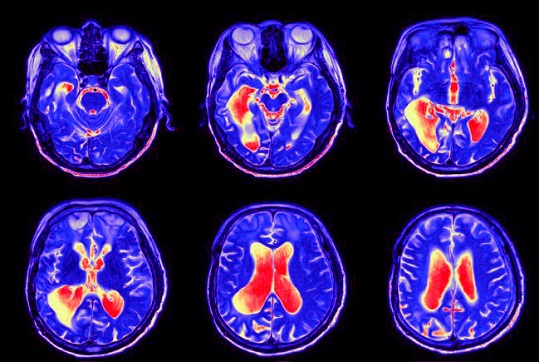

Researchers from the University of Iowa’s Carver College of Medicine have released a comprehensive review exploring how SARS-CoV-2 affects the brain and nervous system. The study reveals that the neurological complications linked to both acute COVID-19 and long COVID are more likely caused by chronic immune-driven inflammation and blood–brain barrier (BBB) damage rather than direct viral infection of brain cells. This Medical News report highlights that persistent glial activation—an immune response by brain support cells—and microvascular injury may explain why many people continue to experience “brain fog,” memory loss, and fatigue months after recovering from the virus.

According to the Iowa research team, while traces of viral RNA and proteins have been detected in autopsied human brains, they appear in low quantities and are unevenly distributed, suggesting the virus does not replicate significantly in neural tissue. Instead, systemic inflammation triggered by the so-called “cytokine storm” during infection disrupts the integrity of the BBB, allowing immune cells and inflammatory molecules to leak into the brain. This process activates microglia and astrocytes—two key glial cell types that, when chronically stimulated, can cause neuronal damage, impaired signaling, and lasting cognitive dysfunction. Animal studies confirm that even after the virus is cleared from the body, the brain remains inflamed and structurally altered for weeks to months, mirroring the human long COVID experience.

Glial Cells and the Blood Brain Barrier Hold the Key

The study provides a framework for understanding why some individuals experience lasting brain-related symptoms despite testing negative for the virus. By comparing autopsy data, imaging results, and animal experiments, the scientists conclude that persistent glial activation and neurovascular inflammation form the biological basis for post-acute neurological syndromes. They warn that elderly individuals and those with diabetes or preexisting brain conditions may face higher risks of long-term damage due to heightened inflammatory responses. Future treatments may need to focus on anti-inflammatory agents that specifically protect the BBB and normalize glial function.